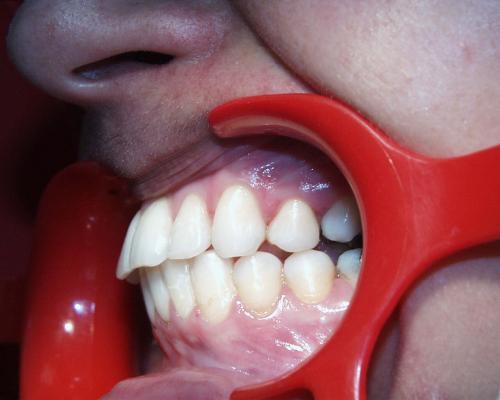

Links Zustand beim Einsetzen der festen Zahnspange, rechts Situation unmittelbar nach der Operation (nach 2 Jahren, 4 Monaten). Der Unterkiefer wurde chirurgisch vorgesetzt und dadurch die Zahnreihen besser in Kontakt gebracht. Die Operation wurde an der Uniklinik Homburg durchgeführt. Eine Feineinstellung der Verzahnung ist aber im Laufe der kieferorthopädischen Nachbehandlung noch erforderlich.